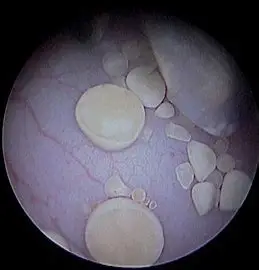

La fibroscopie digestive et respiratoire (y compris la rhinoscopie) ainsi que la cystoscopie sont des techniques de diagnostic et de traitement essentielles en médecine vétérinaire. Elles permettent d’explorer l’intérieur du corps de votre animal de manière non invasive, en utilisant des voies naturelles ou de très petites incisions. Ces procédures sont particulièrement utiles pour localiser et retirer des corps étrangers tels que des épillets coincés dans les voies respiratoires, digestives ou urinaires, ainsi que pour traiter des problèmes comme les calculs vésicaux.

Ces méthodes minimisent les traumatismes pour votre animal, réduisent les risques liés à des chirurgies plus invasives, et favorisent une récupération rapide. En utilisant ces techniques modernes, nous vous offrons des soins de haute qualité avec un maximum de confort pour votre compagnon.